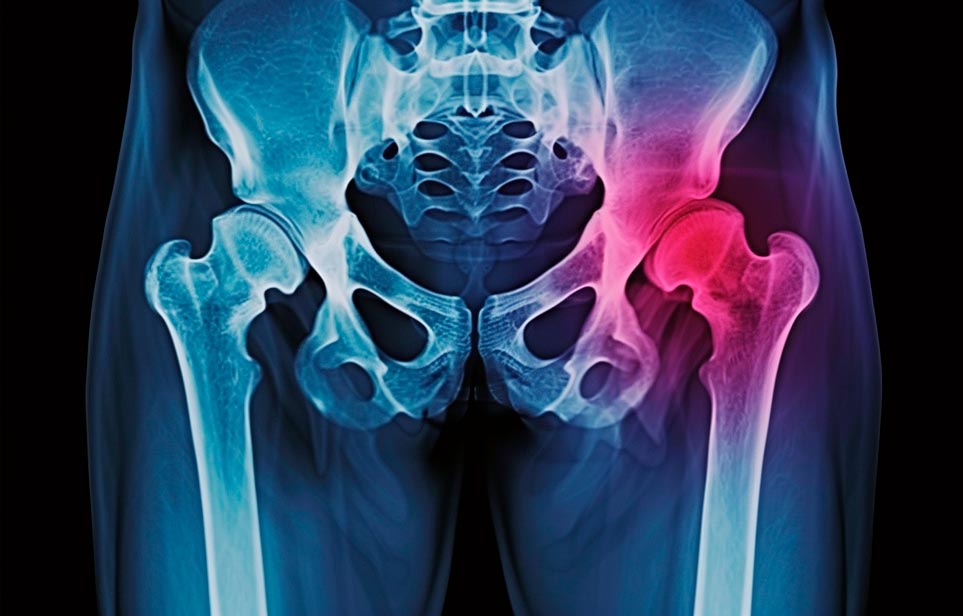

Реабилитация пожилых после перелома шейки бедра в Тюмени

Эффективная и профессиональная реабилитация после перелома шейки бедра в Тюмени осуществляется по демократичным ценам лучшими специалистами современной медицинской клиники «Заботливые люди» с применением персонального подхода к каждому пожилому человеку с такой тяжёлой травмой бедренной кости ноги. В процессе осуществления такой специализированной услуги все наши пациенты имеют возможность получения качественного и достойного обслуживания, эффективного восстановления. Лучший дом престарелых позаботиться о Вашем близком человеке.

Такая травма в большей части случаев возникает у граждан преклонного возраста. При её появлении на протяжении длительного времени сохраняются болевые и неприятные ощущения в области паха, при которых серьёзно ухудшается качество жизни, возникает множество последствий для его жизни и здоровья.

По какой симптоматике можно определить перелом шейки бедра

- Визуально повреждённая нога сокращается на несколько сантиметром из-за сокращения мышц.

- Стопа выворачивается наружу.

- В лежачем положении человек не может поднять ногу.

При такой симптоматике важно незамедлительно обращаться к специалистам для получения всей необходимой помощи, терапии и восстановления после перелома шейки бедра. Если не оказать помощи старику, то это приведёт к гноению, инвалидности, иным видам осложнений.